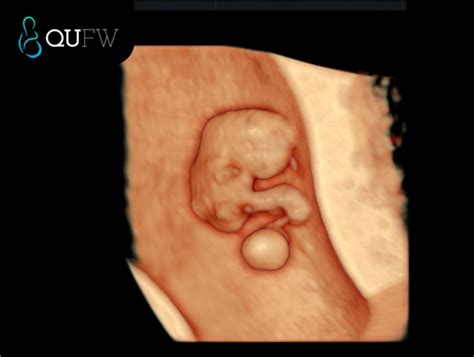

An 8 weeks pregnant sonogram is typically performed transvaginally to get a clearer view of the uterus and the developing embryo. Here are some key points to expect:

• Embryo Size: At 8 weeks, the embryo is about the size of a raspberry, measuring approximately 16 to 18 millimeters in length.

• Heartbeat: One of the most exciting moments is hearing your baby's heartbeat. By this week, the heartbeat is usually detectable and can be seen on the sonogram.

• Developmental Milestones: The embryo's tail is disappearing, and the head makes up nearly half of the embryo's length. The neural tube, which will develop into the brain, spinal cord, and nervous system, is closing.

• Organ Formation: The early stages of organ development are visible. The heart is beating more strongly, and the liver, pancreas, and lungs are beginning to form.